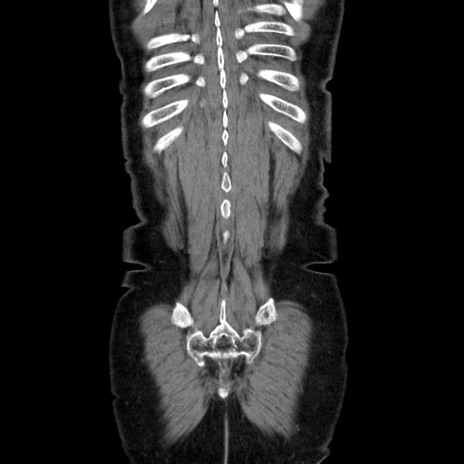

症例5(冠状断像)

【症例】70歳代女性

【主訴】お腹が張る

【現病歴】1週間くらい前から腹部膨満の自覚あり。昨日夜から増悪したため、本日救急外来受診。

【身体所見】意識清明、BT 36.5℃、BP 165/106mmHg、HR 80bpm、SpO2 98%、腹部:膨満、軟、自発痛・圧痛なし、触診にて不快感あり、腸蠕動音:減弱

【データ】WBC 12600、CRP 1.04